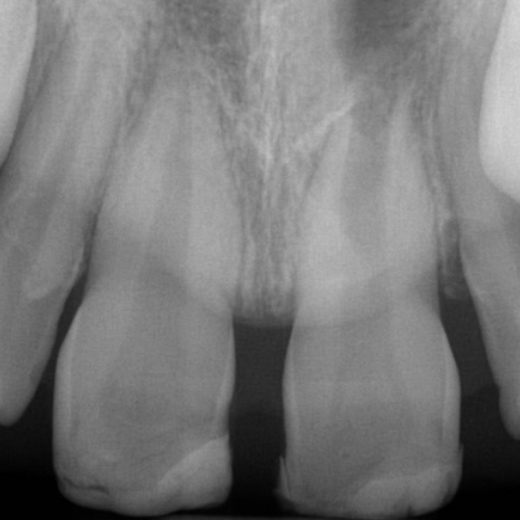

Fallbeispiel: Frontzahntraumata-Trauma im Alter von 9 Jahren mit Recall nach 22 Monaten

Frontzahntraumata sind im Kinder- und Jugendalter nicht selten. Bei noch nicht abgeschlossenem Wurzelwachstum können solche Zähne erfolgreich mit einer Revaskularisation behandelt und erhalten werden.